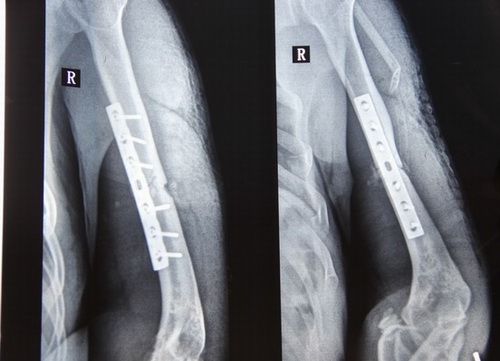

鑒于事故發(fā)生到現(xiàn)在已過(guò)了三十七個(gè)年頭,靖邊縣水利局及有關(guān)單位未向張耀本人做過(guò)任何處理決定,這視為用人單位未作任何處理,同時(shí)證明在當(dāng)時(shí)沒(méi)有與勞動(dòng)者簽訂書(shū)面勞動(dòng)合同的事實(shí),但是以事實(shí)勞動(dòng)關(guān)系認(rèn)定勞動(dòng)關(guān)系確實(shí)存在。事實(shí)勞動(dòng)觀察的成立要件就是勞社部發(fā)[2015]12號(hào)文件通知精神。用人單位招用勞動(dòng)者未訂立勞動(dòng)合同,但同時(shí)具備下列情形的,勞動(dòng)關(guān)系成立。(一)用人單位和勞動(dòng)者符合法律、法規(guī)的主體資格。(二)用人單位依法制定的各項(xiàng)勞動(dòng)規(guī)章制度適用于勞動(dòng)者,勞動(dòng)者受用人單位的勞動(dòng)管理,從事用人單位安排的有報(bào)酬的勞動(dòng)和社會(huì)保障部辦公室《關(guān)于農(nóng)民工適用勞動(dòng)法有關(guān)問(wèn)題的復(fù)函勞社廳函[2013]180號(hào)規(guī)定,凡與用人單位建立勞動(dòng)關(guān)系的農(nóng)民工(包括農(nóng)民輪換工)應(yīng)當(dāng)適用《勞動(dòng)法》,發(fā)生工傷時(shí),應(yīng)適用《企業(yè)職工工傷保險(xiǎn)行政辦法》。2003年4月27日中華人民共和國(guó)國(guó)務(wù)院令第375號(hào)《工傷保險(xiǎn)條例》第十四條(一)款在工作時(shí)間和工作場(chǎng)所內(nèi),因工作原因受到事故傷害的應(yīng)當(dāng)認(rèn)定為工傷。第二十一條,職工發(fā)生工傷經(jīng)治療傷情相對(duì)穩(wěn)定后存在殘疾,影響勞動(dòng)能力的,應(yīng)當(dāng)進(jìn)行勞動(dòng)能力鑒定。張耀同志因殘疾多年疼痛難忍,右胳膊肌肉萎縮,經(jīng)靖邊縣中醫(yī)藥復(fù)查為右面肱骨干粉碎性骨折,內(nèi)固定鋼板保留,榆林市高科法醫(yī)鑒定為右肱骨干陳舊性粉碎性骨折并骨不連影響功能,評(píng)定為八級(jí)傷殘。